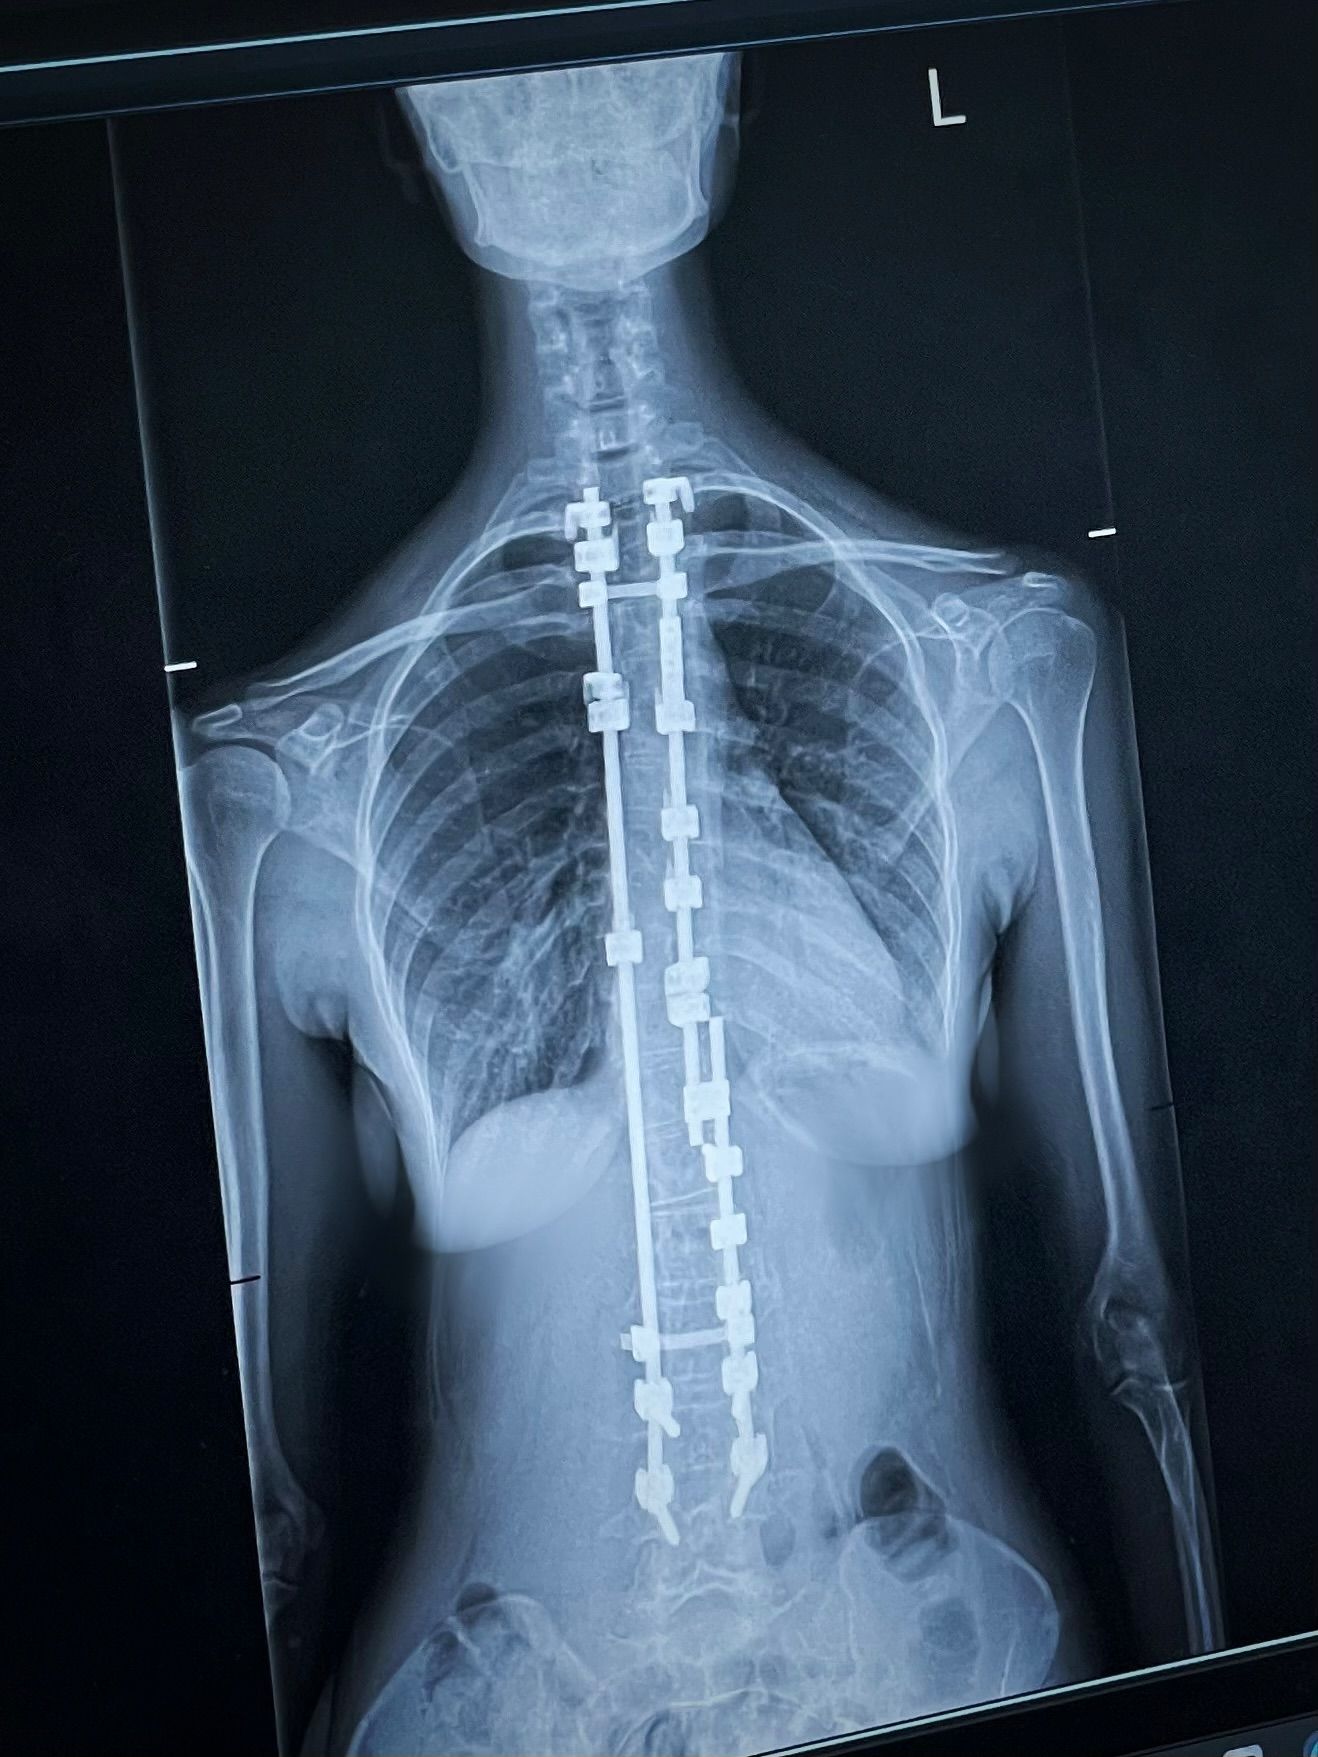

وتُعرف زينة مكّي بشفافيّتها في الحديث عن رحلتها مع مرض الجنف، إذ كانت قد خضعت لعمليّة جراحيّة دقيقة في عمودها الفقريّ خلال فترة مراهقتها، ولم تتردّد في مشاركة تفاصيل هذه التّجربة مع جمهورها، ما جعلها مصدر إلهام للكثير من المرضى، خاصّة من فئة الشّباب.